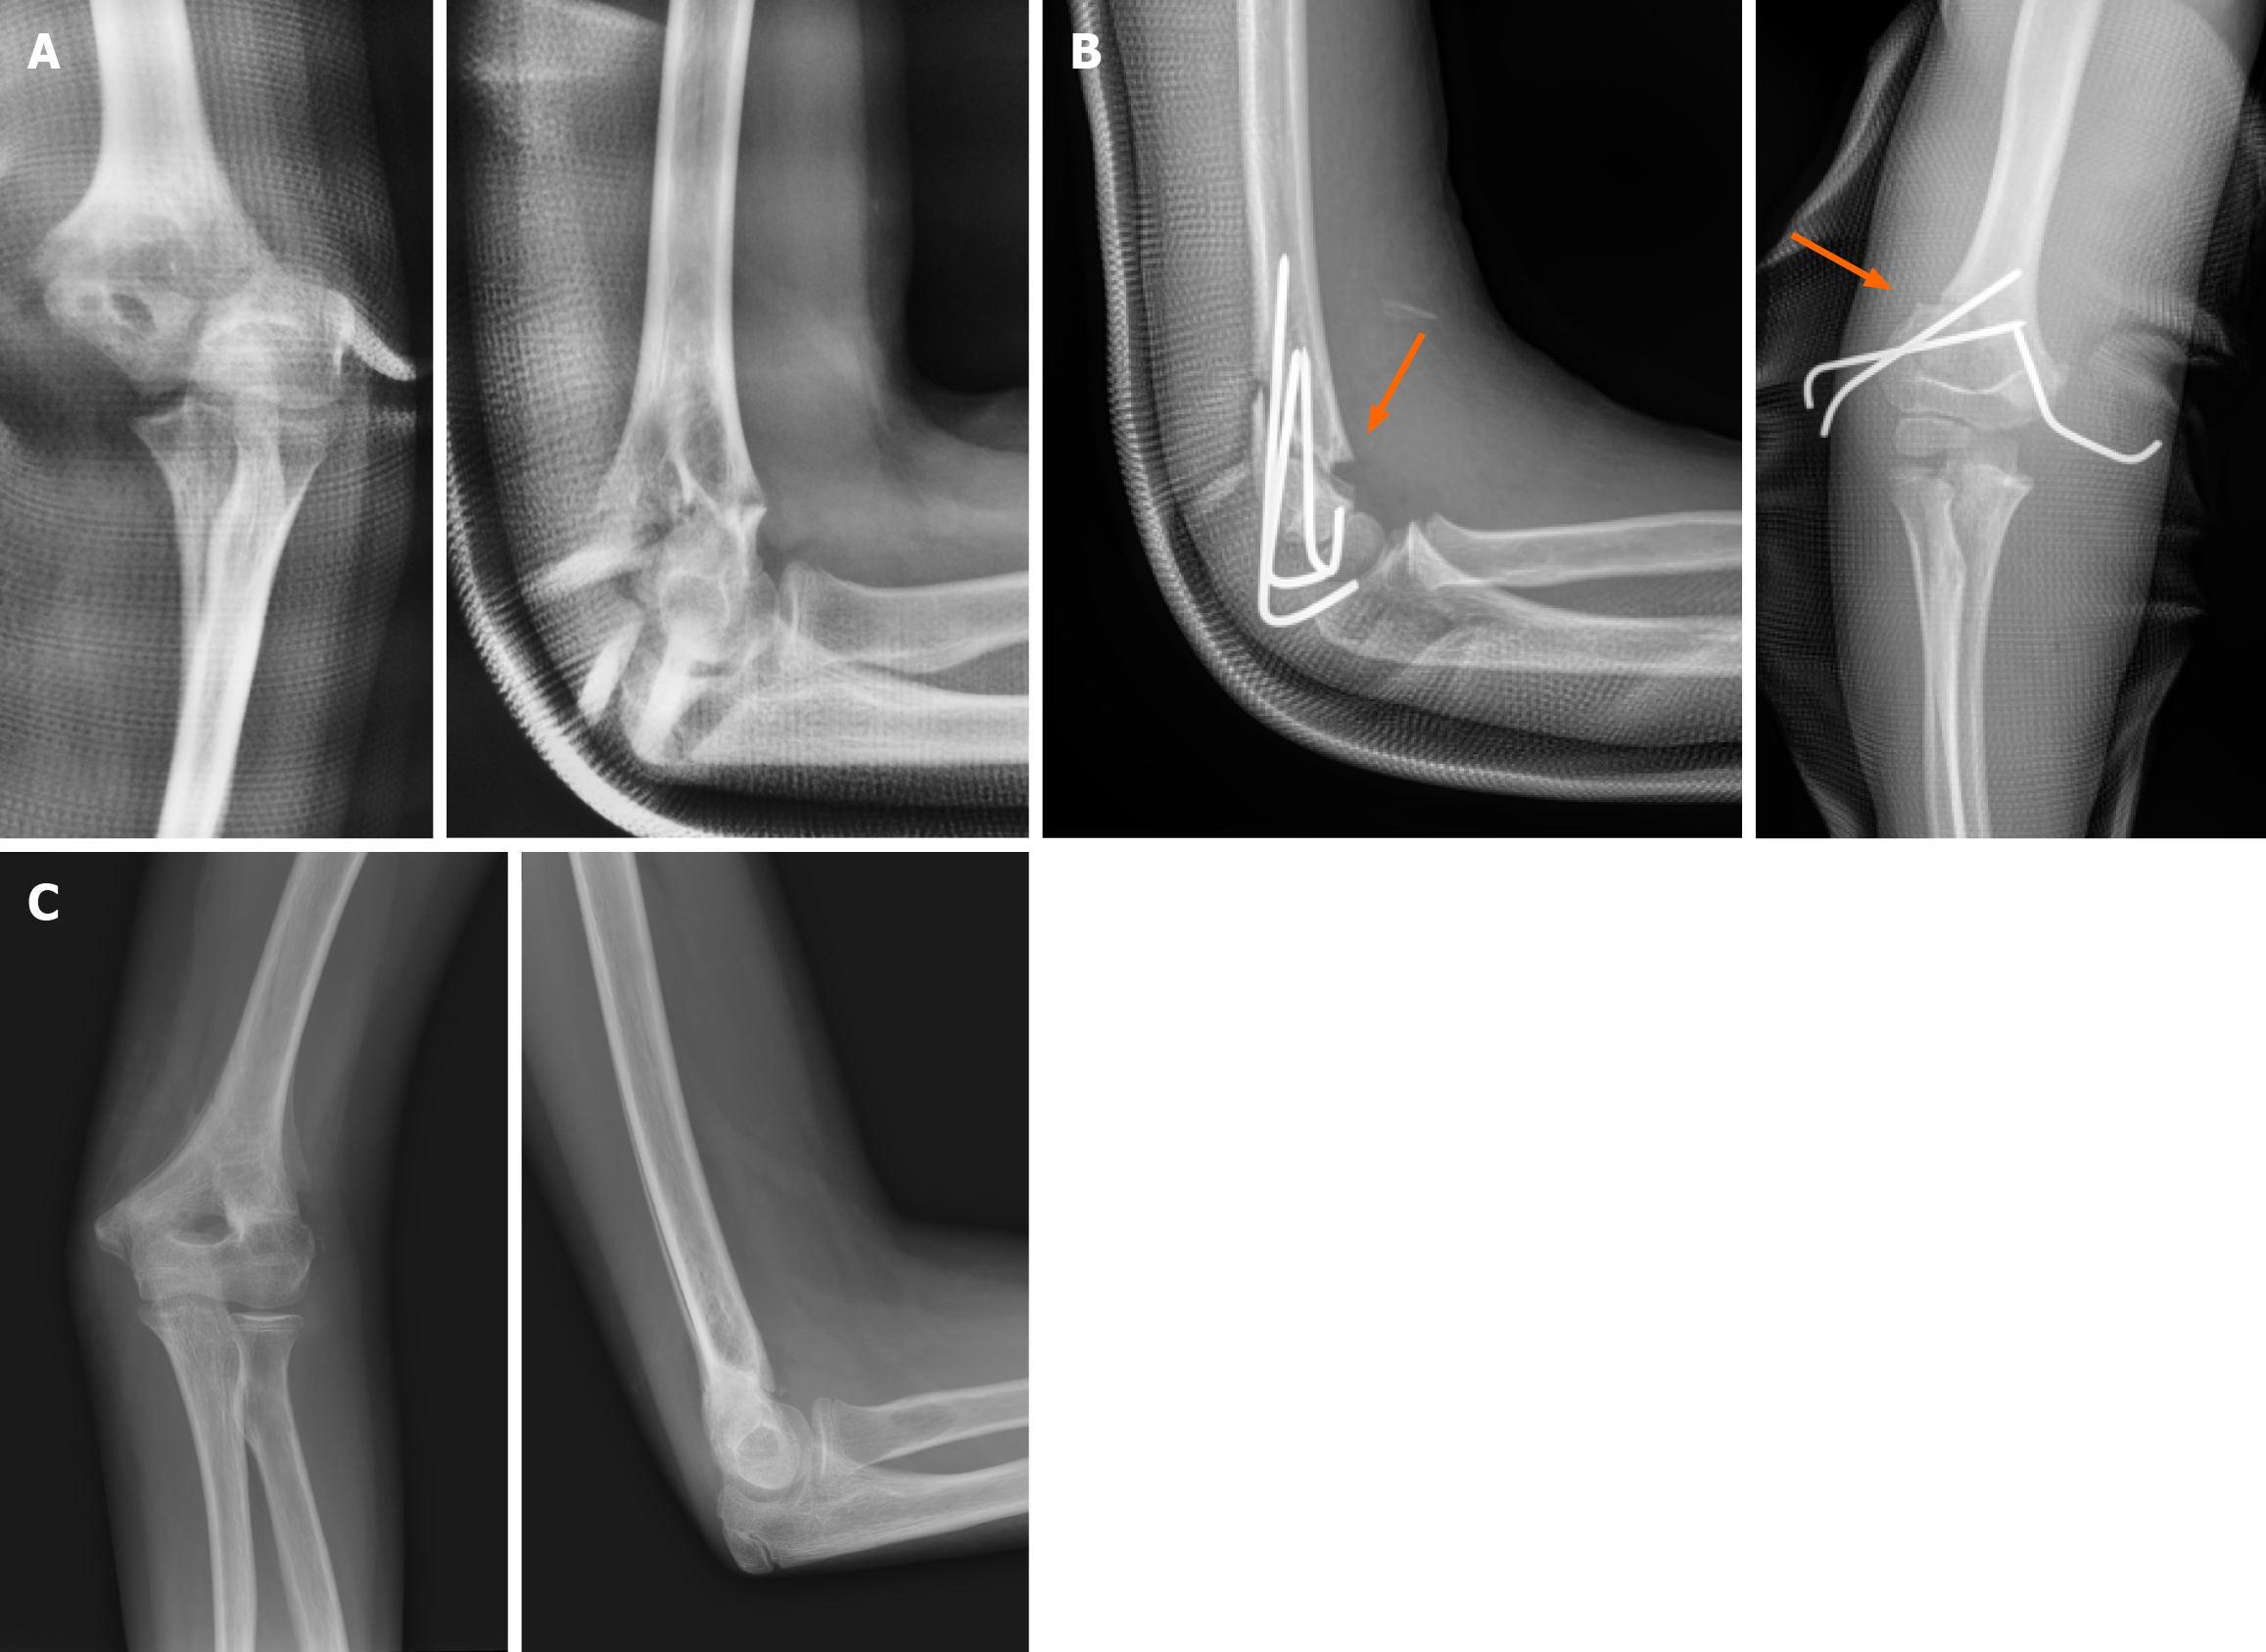

Figure 4 Deformity can be the result of improper reduction or physeal growth arrest (traumatic and iatrogenic).

A: A 7-year-old male with a Gartland type III supracondylar humeral fracture; B: Open reduction via lateral approach and stabilization by 3 Lateral K-wires with incomplete reduction on axial and sagittal level; C and D: In 9-year follow-up there is significant (28°) valgus deformity marked on X-rays (in comparison with the contralateral elbow); E: Elbow range of motion is normal during physical examination.